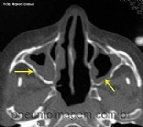

REVISÃO APONTA OS MELHORES DISPOSITIVOS E TÉCNICAS DE APLICAÇÃO DE MEDICAMENTOS NASAIS.

Os tratamentos tópicos estão sendo comumente empregados para a gestão da rinite e da rinossinusite crônica (RSC) dado o potencial de aumento da atividade das drogas no local e de se evitar os efeitos colaterais sistêmicos. Considerando que ...